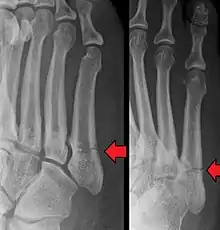

- Proximal diaphysis, typically stress fracture.[12][13]

- Metaphysis: Jones fracture[14]

-Tuberosity: Pseudo-Jones fracture[15] (avulsion fracture).[15]

Other proximal fifth metatarsal fractures exist, although they are not as problematic as a Jones fracture. If the fracture enters the intermetatarsal joint, it is a Jones fracture. If, however, it enters the tarsometatarsal joint, then it is likely an avulsion fracture caused by pull from the fibularis brevis tendon. An avulsion fracture at the base of the fifth metatarsal is sometimes called a "dancer's fracture" or a "pseudo Jones fracture", and usually responds readily to non-operative treatment.[18] The X-ray appearance of the developmental "apophysis" in this area may have some resemblance of a fracture, but is not a fracture; it is the secondary ossification center of the metatarsal bone. It is a normal finding that occurs at this site in adolescents.[19] If an injury to that area has occurred, the physician is often able to interpret certain radiographic clues to make the differentiation. An avulsion fracture at this location is typically extra-articular and oriented transversally as compared to the longitudinal orientation of an unfused apophysis.[19]

For several reasons, a Jones fracture may not unite. The diaphyseal bone (zone II), where the fracture occurs, is an area of potentially poor blood supply, existing in a watershed area between two blood supplies. This may compromise healing. In addition, there are various tendons, including the fibularis brevis and fibularis tertius, and two small muscles attached to the bone. These may pull the fracture apart and prevent healing.

Zones I and III have been associated with relatively guaranteed union and this union has taken place with only limited restriction of activity combined with early immobilization. On the other hand, zone II has been associated with either delayed or non-union and, consequently, it has been generally agreed that fractures in this area should be considered for some form of internal immobilization, such as internal screw fixation.

These zones can be identified anatomically and on x-ray adding to the clinical usefulness of this classification.[21] Surgical intervention is not, by itself, a guarantee of cure and has its own complication rate. Other reviews of the literature have concluded that conservative, non-operative, treatment is an acceptable option for the non-athlete.[22]